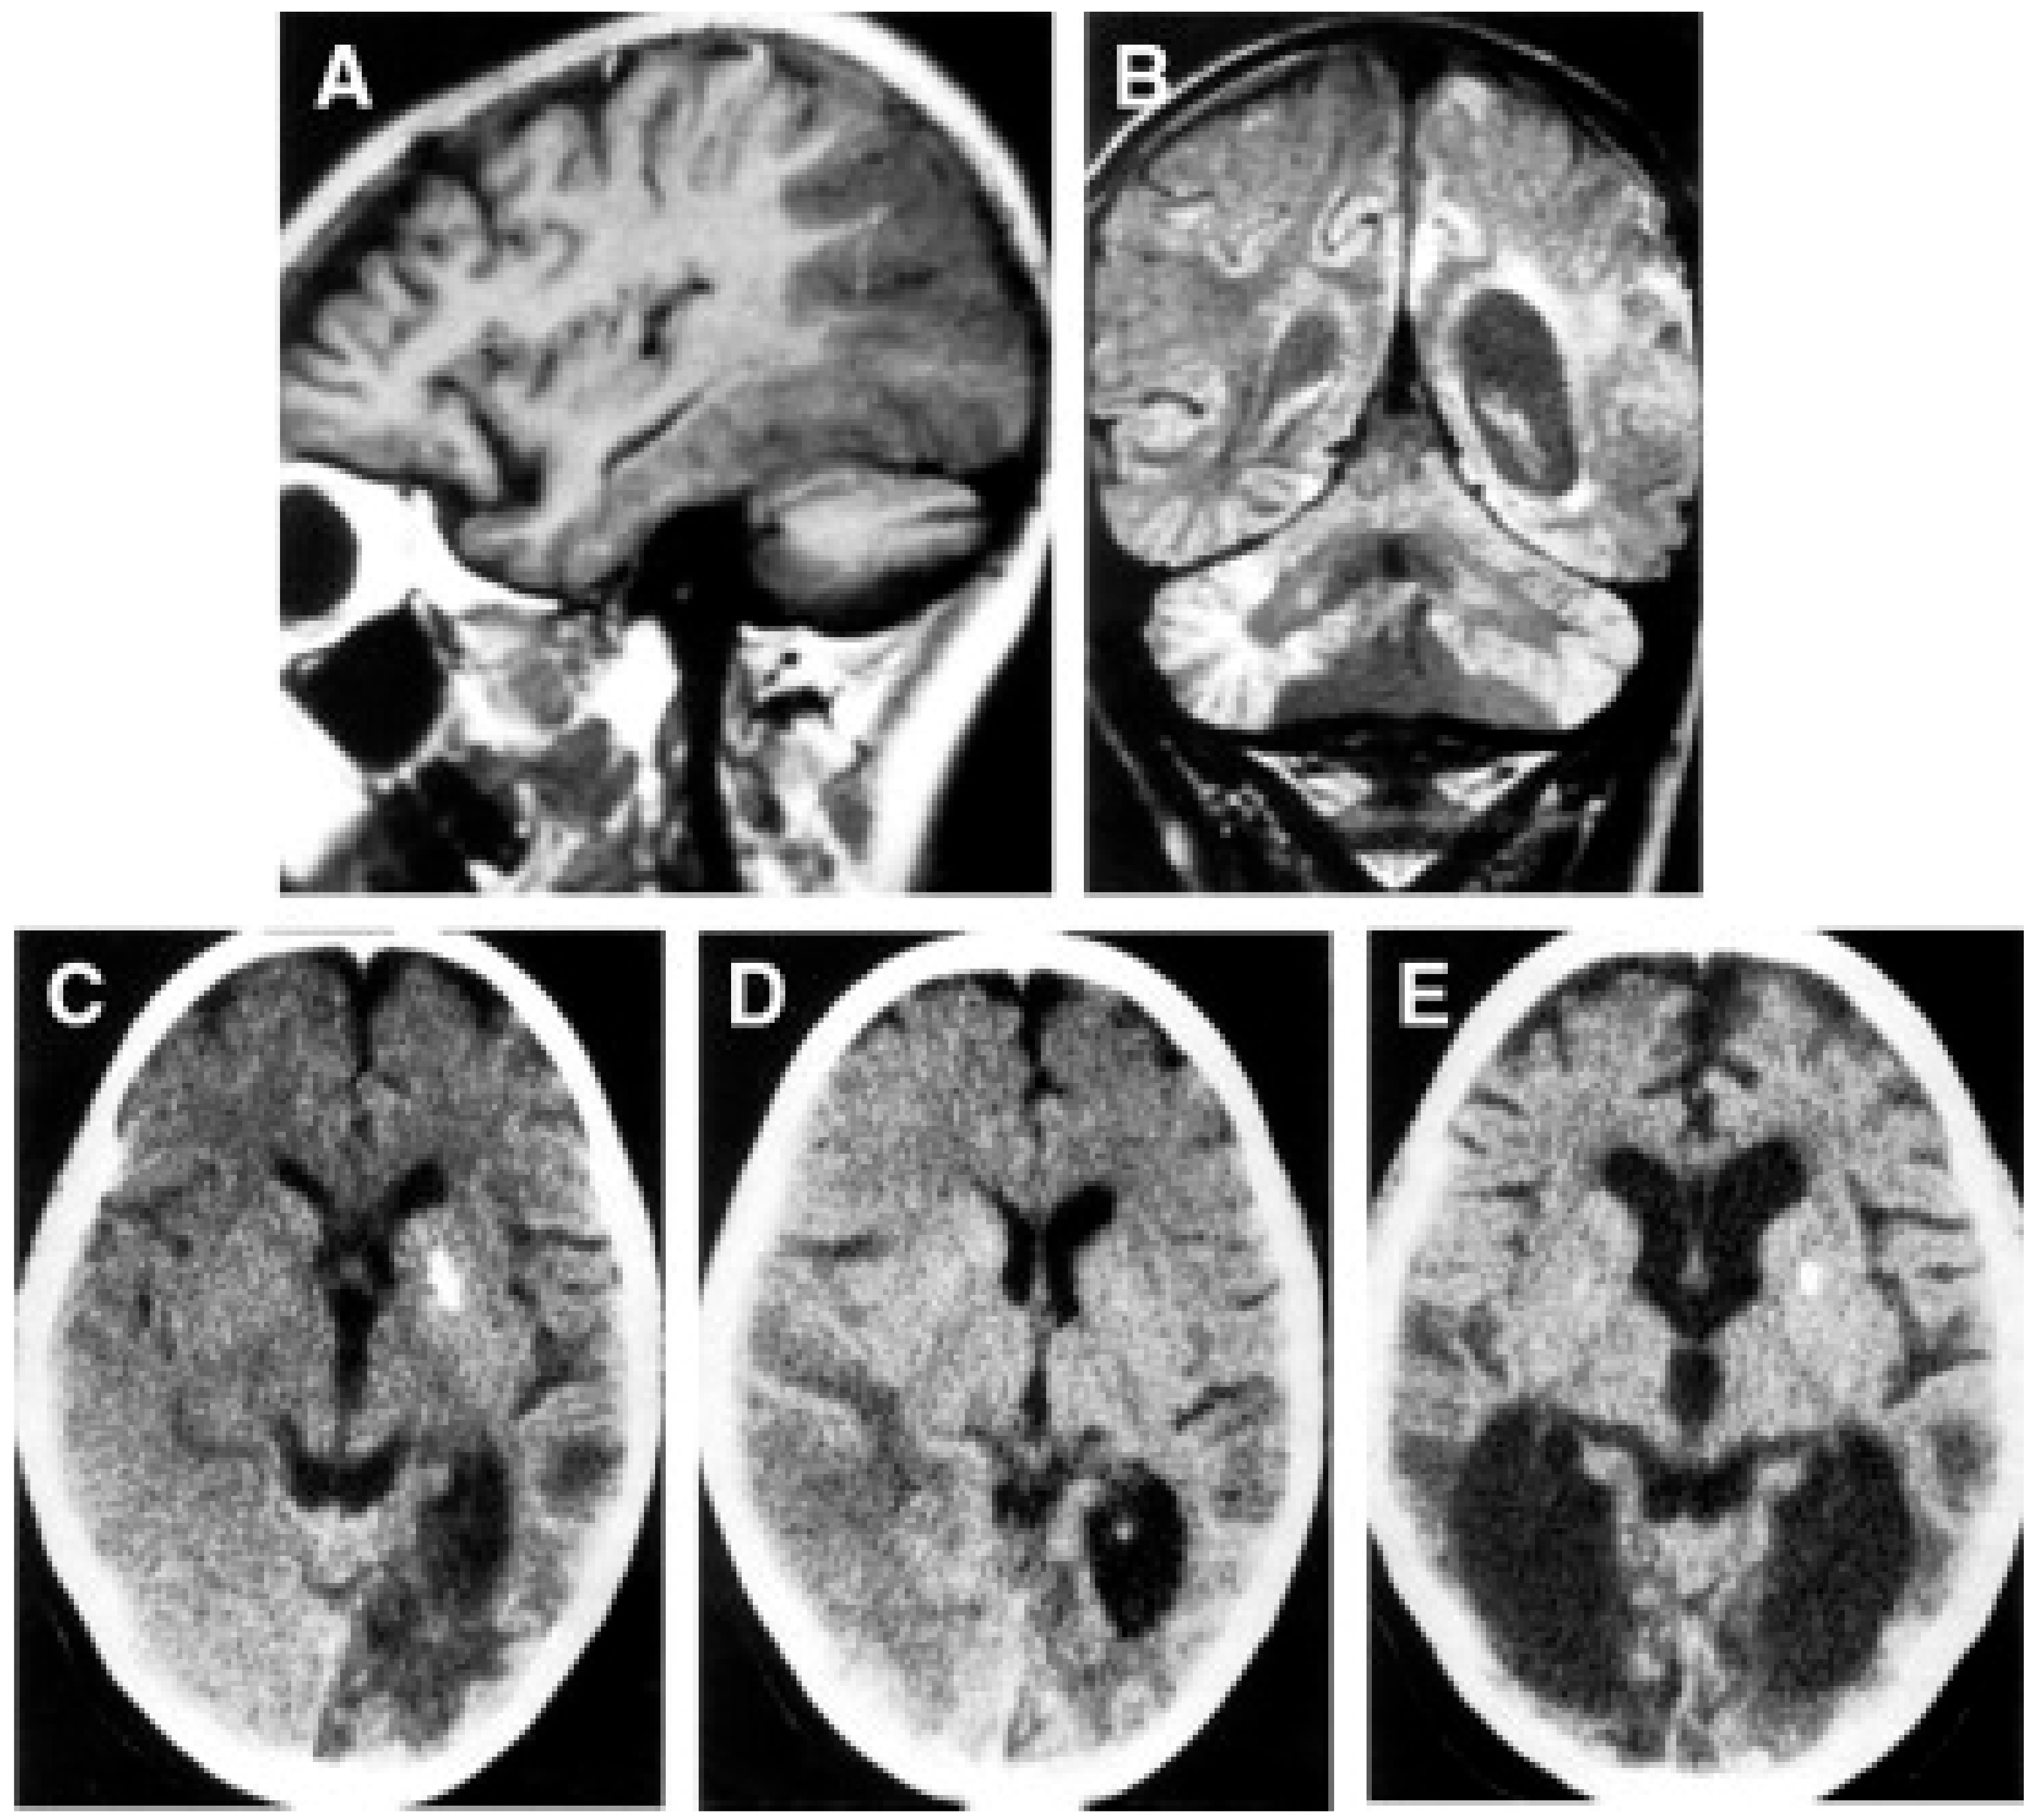

- Goto, Y.; Nonaka, I.; Horai, S. A Mutation in the TRNALeu(UUR) Gene Associated with the MELAS Subgroup of Mitochondrial Encephalomyopathies. Nature 1990, 348, 651–653. [Google Scholar] [CrossRef] [PubMed]

- Hirano, M.; Ricci, E.; Koenigsberger, M.R.; Defendini, R.; Pavlakis, S.G.; DeVivo, D.C.; DiMauro, S.; Rowland, L.P. Melas: An Original Case and Clinical Criteria for Diagnosis. Neuromuscul. Disord. 1992, 2, 125–135. [Google Scholar] [CrossRef]

- Savoiardo, M.; Bruzzone, M.G.; D’Incerti, L.; Farina, L.; Grisoli, M. Metabolic and Genetic Diseases of the Brain. Riv. Neuroradiol. 1999, 12, 73–86. [Google Scholar] [CrossRef]

- Mizukami, K.; Sasaki, M.; Suzuki, T.; Shiraishi, H.; Koizumi, J.; Ohkoshi, N.; Ogata, T.; Mori, N.; Ban, S.; Kosaka, K. Central Nervous System Changes in Mitochondrial Encephalomyopathy: Light and Electron Microscopic Study. Acta Neuropathol. 1992, 83, 449–452. [Google Scholar] [CrossRef]

- Tsuchiya, K.; Miyazaki, H.; Akabane, H.; Yamamoto, M.; Kondo, H.; Mizusawa, H.; Ikeda, K. MELAS with Prominent White Matter Gliosis and Atrophy of the Cerebellar Granular Layer: A Clinical, Genetic, and Pathological Study. Acta Neuropathol. 1999, 97, 520–524. [Google Scholar] [CrossRef]